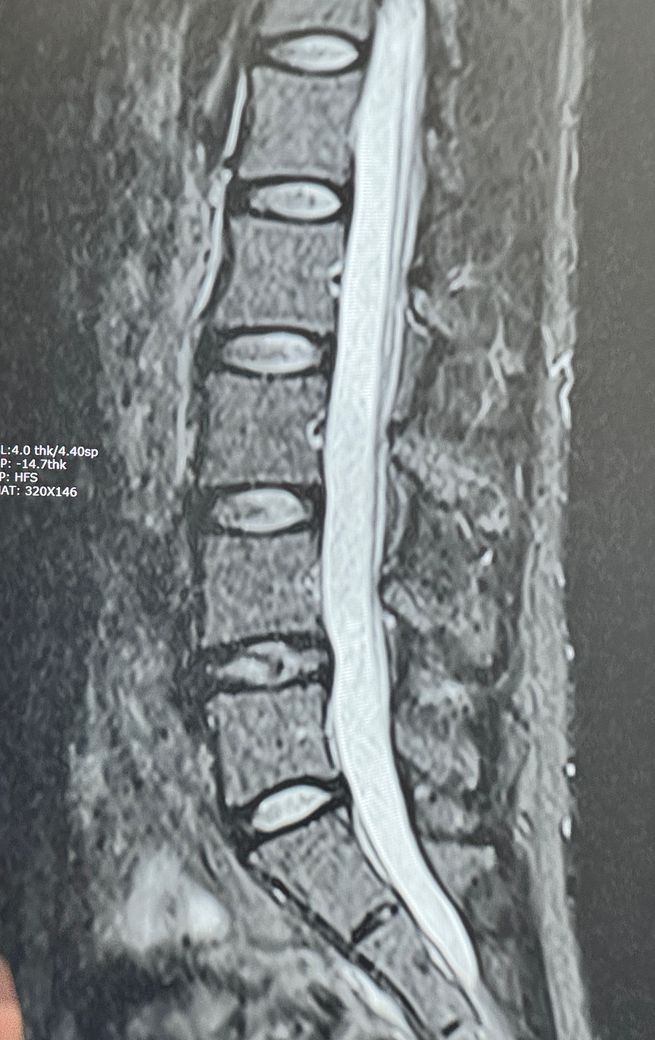

MRI 한번만 봐주세요. 심각한건가요?

의사쌤 말로는 4-5번 디스크가 터졌다고 하나 수술할 정도나 걱정할 정도는 아니고 그냥 쉬면 된다 하는데 생각보다 방사통이 심합니다..

사진은 급한대로 이렇게밖에 없어 죄송합니다.

• 1번 째 사진